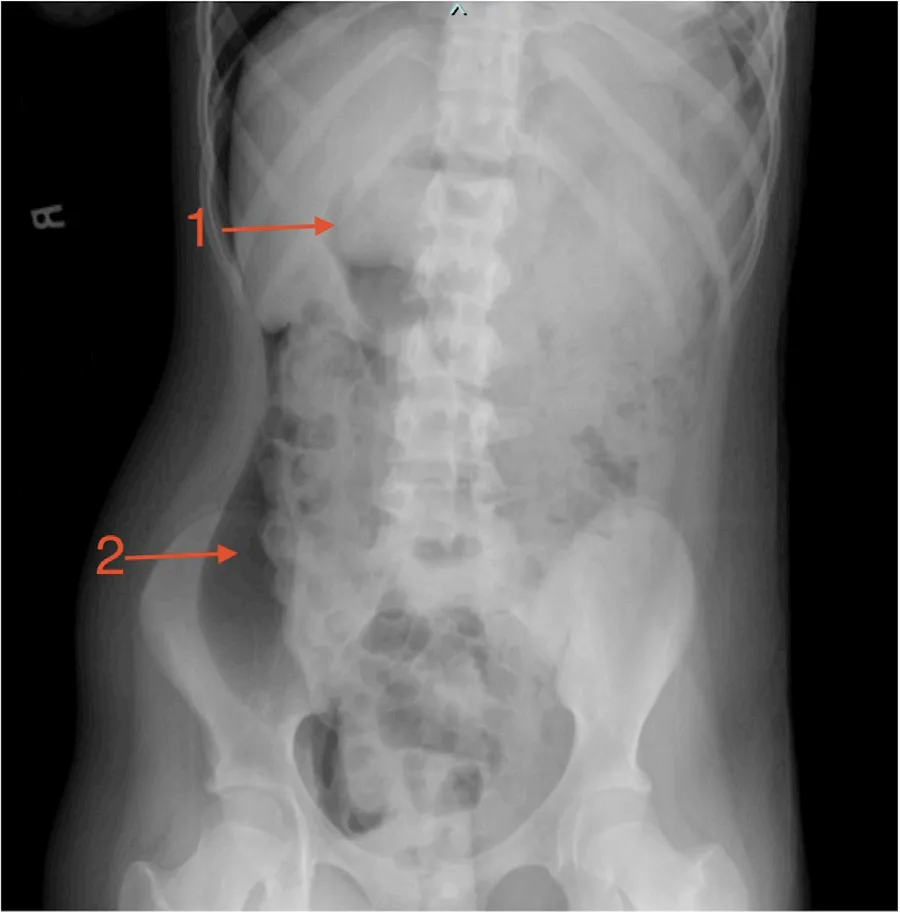

在过去一年中,患儿体重下降30磅,并出现进行性乏力和腹胀。入院时体温正常,生命体征符合其年龄特征。查体可见中线/上腹部存在明显肿块,实验室检查显示

图1